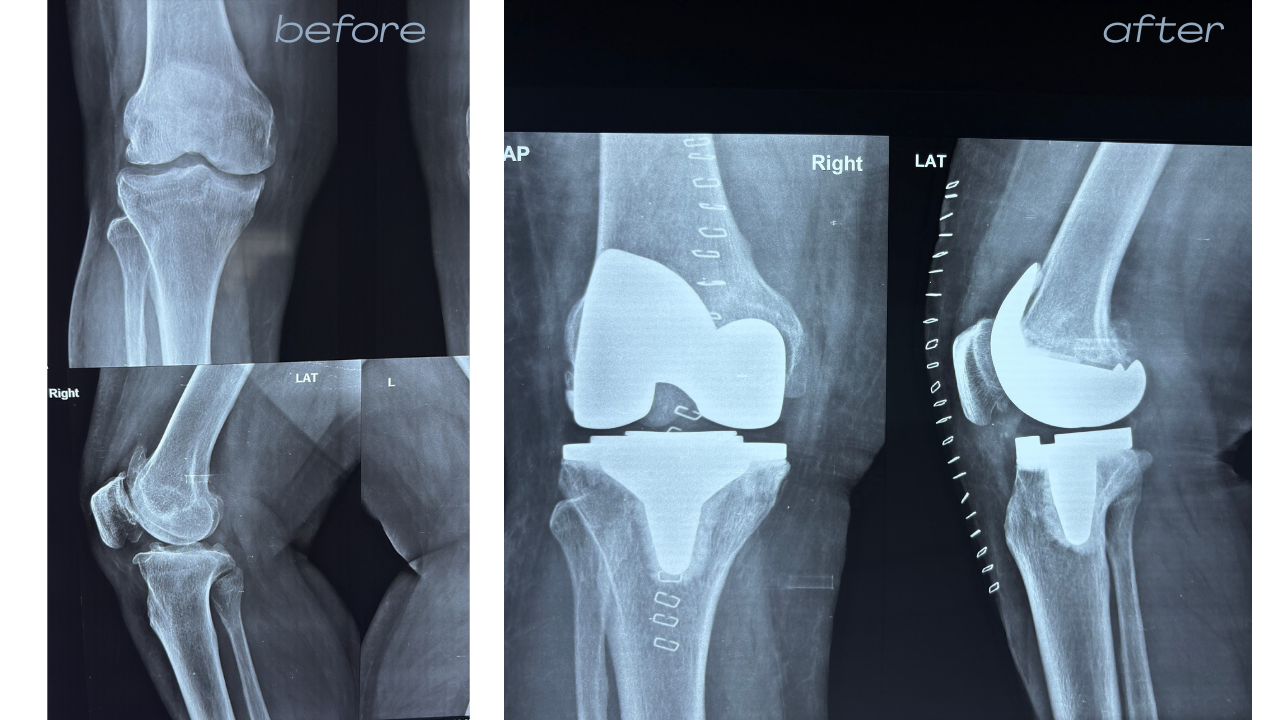

- Knee & Joint Care:

Specialist in Pain & Replacement.

Over 8,000 successful orthopedic procedures, ranging from complex trauma to total joint replacements.